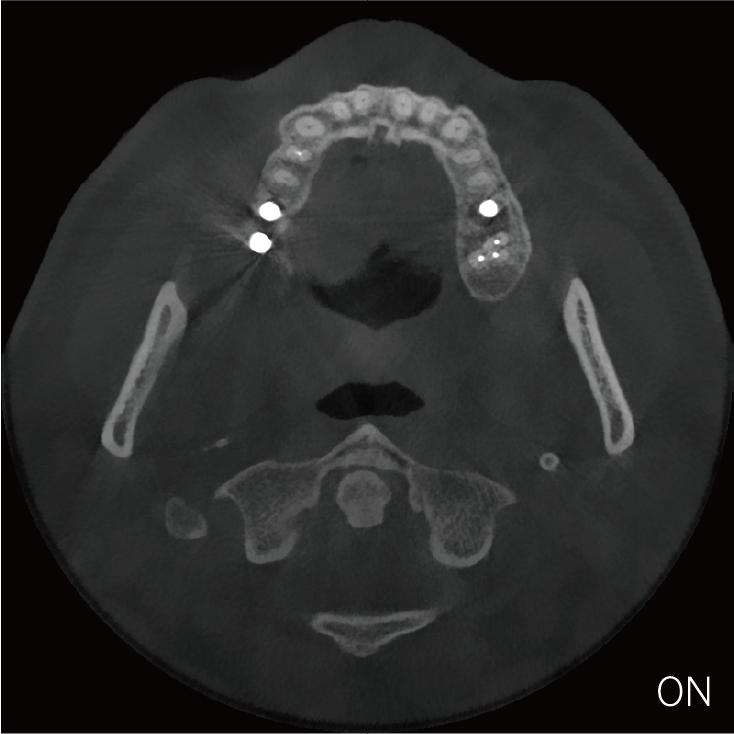

局部超清显示、 移动视野摄片

可根据临床需求任意调整成像区域大小实现局部超清三维显示

临床样片